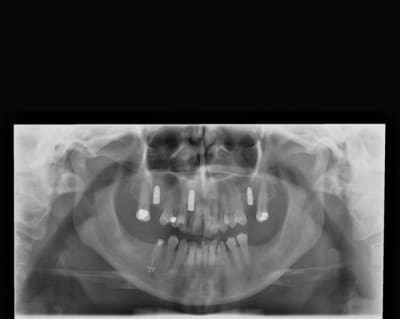

pxav

28/08/2009 à 18h44

le pano

--

xbk

28/08/2009 à 18h47

Céramik écrivait:

> Céramik

Voila mon ami